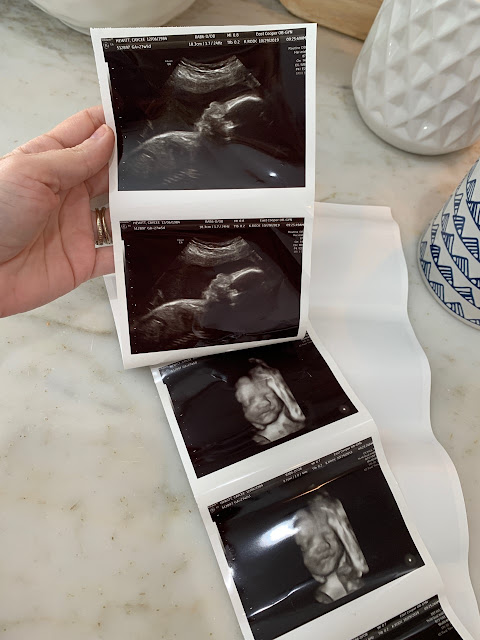

We had another ultrasound this week and it was so exciting to get to see our sweet baby girl in my belly. Todd and I are both very excited and so ready for January!!

FOUR //

Speaking of being ready for January, at our appointment we had to make a game plan for her birth. As most of you know, I had to have a c-section with both Carson and Taylor, but this time I’ve been given the go-ahead to try and attempt a v-back. At this point, my percentage is looking pretty good for it being a success, but we really won’t know anything for sure until right before her due date. That being said, if any of you are comfortable sharing, I would LOVE to hear from any of you that have had a successful (or unsuccessful) v-back and what your experience was like.